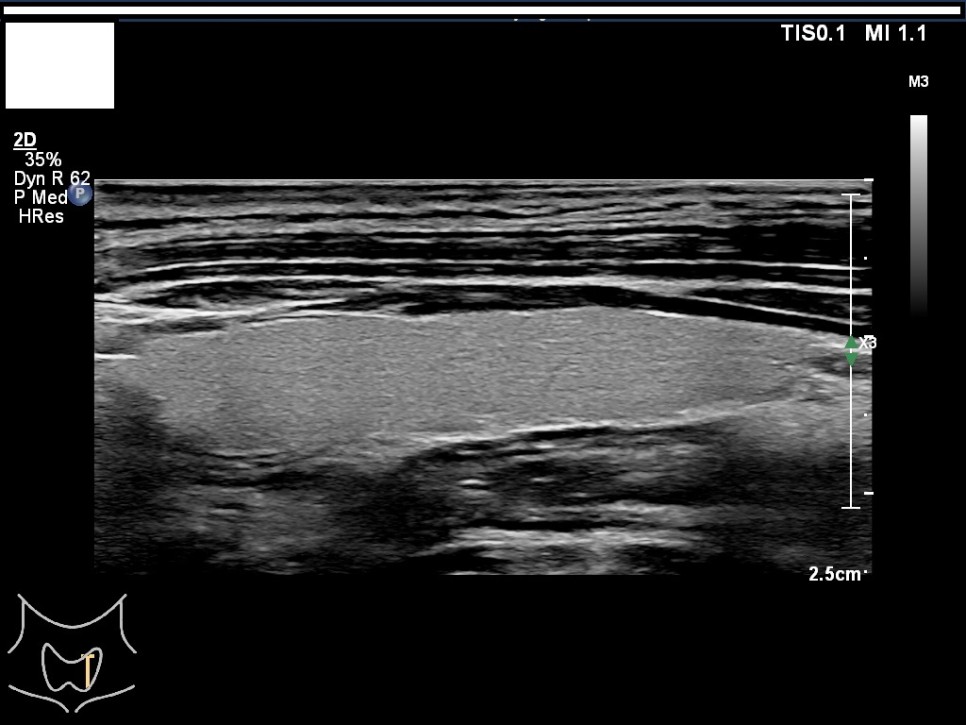

갑상선, 부갑상선 초음파 검사 급여 기준 1. 표준 영상의 범위 모든 영상에는 경부의 해부학적 위치(모식도나 문자)를 표기하여야 한다.

A) 병변이 없는 경우: 우엽 중부 가로 스캔, 우엽 중앙부 세로 스캔, 협부 가로 스캔, 좌엽 중부 가로 스캔, 좌엽 중앙부 세로 스캔, 우경부 림프절, 좌경부 림프절 나) 병변이 있는 경우: 병변이 없는 경우의 표준 영상과 함께 병변 부위에서 2개의 수직 관계 단면 영상(횡단/종단) 및 병변의 크기가 측정된 경우: 병변이 없는 경우의 표준 영상

좌경부 림프절 5/우엽 중부 가로 스캔/우엽 중앙부 세로 스캔

우경부림프절/좌엽중앙세로 스캔/좌엽중앙가로스캔